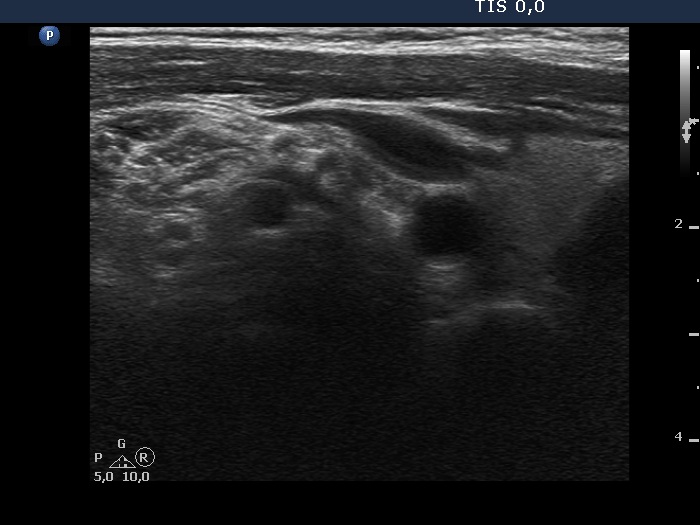

Lateral to the right lobe, another longitudinal scan.